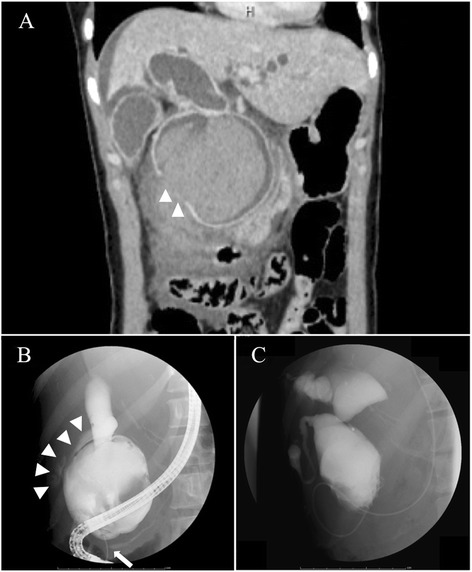

Urgent contrast-enhanced abdominal computed tomography (CT) revealed remarkable dilatation of the CBD. It also demonstrated fluid collection around the CBD, mainly in the retroperitoneal space, and suspicion of a perforated cyst wall (Fig. 1a). Endoscopic retrograde cholangiopancreatography (ERCP) was performed for further evaluation and biliary drainage, with a presumed diagnosis of perforated CC. ERCP revealed APBDU and biliary leakage out of the CC (Fig. 1b). The concentration of amylase in the bile was 2040 IU/L. After an endoscopic nasal biliary drainage (ENBD) tube was placed, the general condition of the patient improved. Before the definitive surgery, additional multimodal examinations, including cholangiography taken by the ENBD tube (Fig. 1c), CT, magnetic resonance cholangiopancreatography, ultrasonography, and pathology tests, revealed a congenital type IVa CC, according to Todani’s classification [ref. 6], but no signs of malignancy.